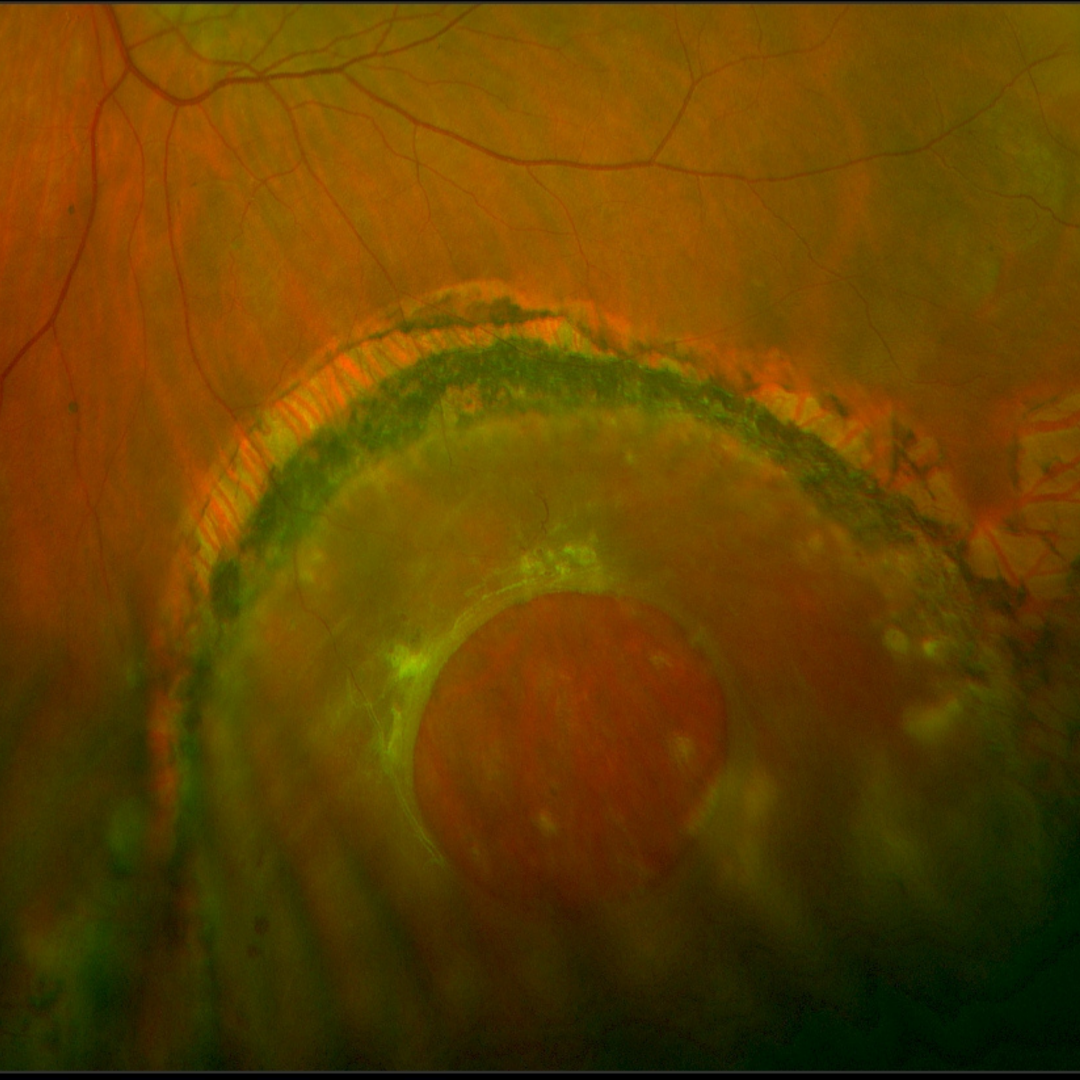

Case 6: Chronic retinal detachment

An asymptomatic 51-year-old Asian male with high myopia and best corrected visual acuity of 6/30-1 (20/100-1) in the right eye and 6/6 (20/20) in the left eye.

Given the chronic nature of the retinal detachments, they are unlikely to require treatment, however this patient was referred to an ophthalmologist for assessment.

Optomap pseudocolour (top) and green separation (bottom) images - right eye

More infoOptomap pseudocolour (top) and green separation (bottom) images - left eye